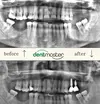

Implant Treatment

Porcelain Applications

Laminate Veneer